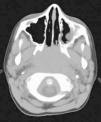

Caso clínicoPaciente de 9 años, varón, sin antecedentes de interés, que consulta en el Servicio de Urgencias por epistaxis. Refiere 10 episodios en los últimos 3 meses, autolimitados, de 10min de duración. Diagnosticado un mes antes de anemia ferropénica en tratamiento. En la exploración destaca una epistaxis activa, palidez mucocutánea, adenopatía laterocervical izquierda de 2×2cm, móvil, de consistencia dura, dolorosa a la palpación, no adherida a planos profundos, sin signos inflamatorios evidentes, controlada por su pediatra, y otras menores de 1cm, submandibulares y cervicales bilaterales. En el resto de la exploración no hubo hallazgos. En Urgencias no se visualiza el punto de hemorragia y se realiza taponamiento anterior. La analítica evidencia anemia ferropénica sin trastornos de la coagulación. Se realiza una tomografía computarizada (TC) maxilofacial, en la que se visualizó una ocupación de la luz del cavum (fig. 1). Se completa el estudio con exploración endoscópica nasal, en la que se visualiza una masa rinofaríngea en pared posterosuperior y se cauteriza con bisturí eléctrico, cediendo la hemorragia. Se toma muestra para biopsia, que da como resultado un carcinoma indiferenciado de cavum (fig. 2). Posteriormente, se envió al paciente al Servicio de Oncología pediátrica para seguimiento y tratamiento con radioterapia.